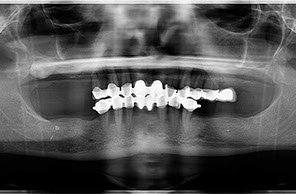

riabilitazione completa su impianti

due casi all on four carico immediato